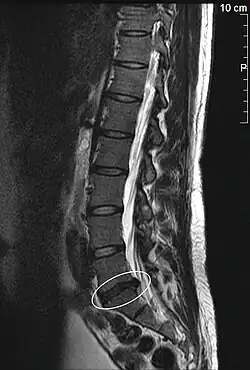

MRT-Aufnahme eines Bandscheibenvorfalls in der Lendenwirbelsäule

Der Bandscheibenvorfall (lateinisch Prolapsus nuclei pulposi, ärztlich oft Nucleus-pulposus-Prolaps, kurz NPP), auch Bandscheibenprolaps (BSP), Bandscheibenhernie, Discushernie (oder Diskushernie) und Discusprolaps, ist eine Erkrankung der Wirbelsäule, bei der Teile der Bandscheibe in den Wirbelkanal – den Raum, in dem das Rückenmark liegt – vortreten. Im Gegensatz zur Bandscheibenprotrusion (Vorwölbung) wird beim Prolaps der Faserknorpelring der Bandscheibe (Anulus fibrosus) ganz oder teilweise durchgerissen, während das hintere Längsband (Ligamentum longitudinale posterius) intakt bleiben kann (sogenannter subligamentärer Bandscheibenvorfall).